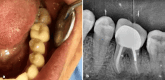

Figure 1

Figure 1. (a) Intraoral view revealing the presence of a periodontal pocket and gingival swelling. (b) Preoperative periapical radiograph showing periapical and interradicular radiolucency. (c) Intraoral view after scaling and drainage of the periodontal abscess.